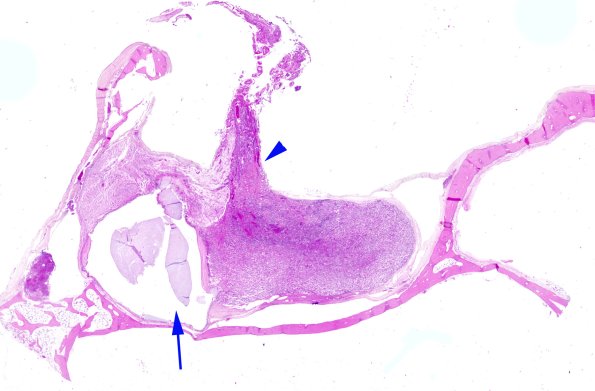

The pituitary showing part of the stalk (arrowhead) and a Rathke cleft cyst (arrow) between the neuro- and adenohypophysis. (H&E)